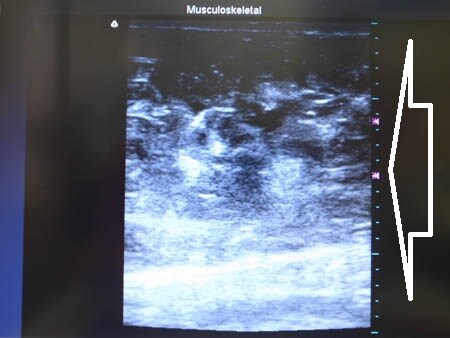

上記の画像の部分をつまんでみましょう。

↓ ↓ ↓

同様に下腹部も見ておきましょう。